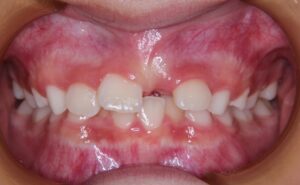

10歳の女児。前歯で食物を咬み切れないことを主訴として来院した。初診時の口腔内写真を次に示す。原因として考えられるのはどれか。1つ選べ。

そもそも前歯で物が咬み切れない原因は開咬によるものです。上記の選択肢から開咬になる原因を探していきましょう。

b. 舌突出癖は上下前歯の間に舌尖を突き出す癖で、前歯部の間に舌が介在しているため前歯部の唇側傾斜や開咬状態となります。

以上より正解はb. 舌突出癖です。